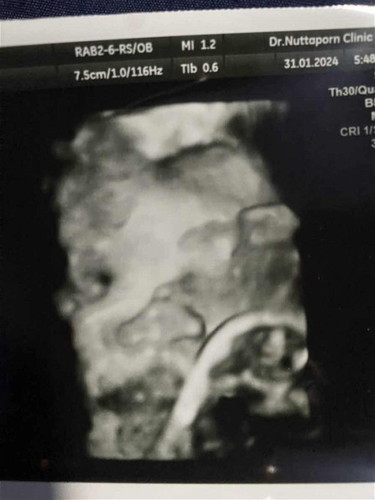

จากภาพอัลตร้าซาวน์น้องมีโอกาสจะเป็นปากแหว่งรึเปล่าคะ ตอนนี้กังวลมากแล้วเวลาซาวน์น้องไม่ยอมให้เห็นหน้าดีๆเลยค่ะ